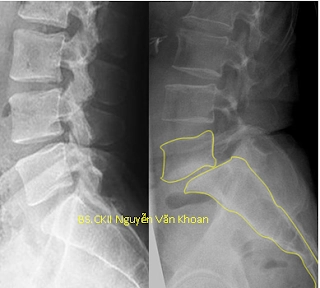

Là tình trạng đốt sống trên trượt ra trước hoặc ra sau so với đốt sống dưới. Tình trạng này khiến bệnh nhân đau thắt lưng, đi đứng khó khăn, và thường đau lan xuống một hoặc hai chân.

Bình thường Trượt đốt sống L5/S1

Hình X quang trên cho thấy trượt đốt sống nặng L5/S1 (hình bên trái). Trượt đốt sống L4/L5 do khuyết eo L4 (hình bên phải).